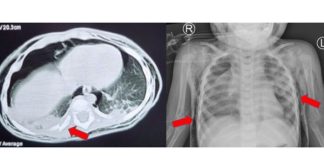

Người đàn ông 52 tuổi q-u-a đ-ờ-i vì tiểu đường, bác...

Vẫn luôn nghĩ mình khỏe mạnh, không ngờ khi đang làm việc, người đàn ông này bỗng ngã ra đất bất tỉnh rồi qua đời không lâu sau đó tại bệnh viện. Ông Chu (52 tuổi, Trung Quốc) luôn nói rằng bệnh tiểu đường là “bệnh của người giàu” và những người làm việc tại [...]